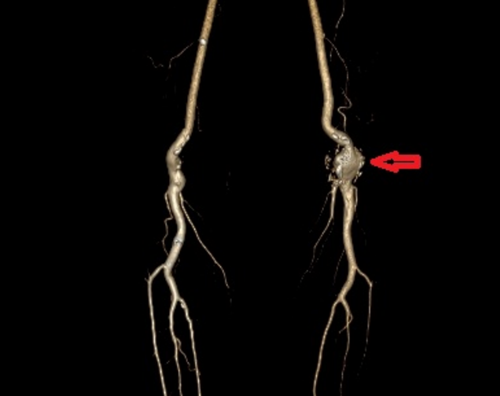

入院后,外周血管介入科主任、主任医师赵扬程详细询问了患者病史并为其进行了全面的体格检查,发现该腘动脉瘤位于左膝盖后方的腘窝处,大小约5 CM×4CM,摸之搏动明显。赵扬程解释,腘动脉位于人体腘窝内,负责向小腿及足部输送血液,腘动脉瘤是由于腘动脉血管壁发生异常扩张,从而形成囊状、球形的病变,并非真正的肿瘤。腘动脉瘤的发病原因尚未清楚,可能由吸烟、外伤、炎症等因素导致血管壁薄弱,动脉在血压的冲击下缓慢发生扩张,从而引起腘动脉瘤。

由于瘤体正好处于膝关节后,介入手术放置支架容易造成支架移位和折断,患者更适合通过血管外科手术方式达到切除动脉瘤和清除瘤腔中的血栓。赵扬程立刻执行多学科协作诊疗方案,邀请副院长、手足显微外科专家、主任医师刘鸣江,风湿免疫科罗徐医师讨论患者的手术方案。刘鸣江院长结合患者影像学检查,详细询问患者病情,仔细检查患者双下肢动脉搏动,浅表静脉走形,腘动脉瘤病灶等情况,同时考虑到患者体型偏瘦,双下肢浅表静脉细的特点,最终确定最优手术方案。